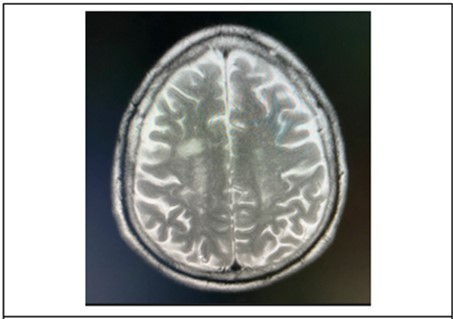

Cranial MRI plain and with contrast was requested by the ophthalmology service to further investigate on the brainstem. The subsequent study done 21 days after onset of symptoms, revealed patchy bright flair signals were noted in the subcortical white matter and periventricular area. (Figure 6) The orbits, midbrain, pons were regarded as unremarkable.

Figure 6.It showing T2 weighted, axial MRI scans at the level of the lateral ventricles, revealed patchy bright flair signals were noted in the subcortical white matter and periventricular area.